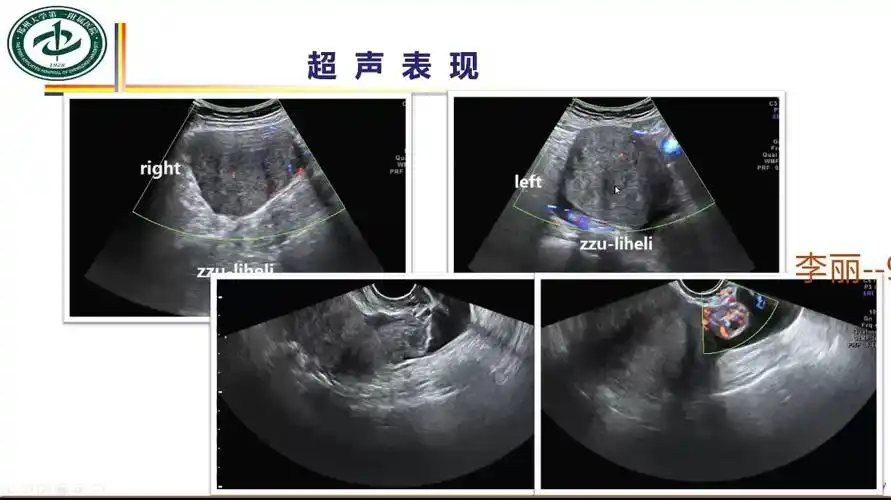

卵巢囊肿蒂扭转两例

女性附件蒂扭转的超声诊断思路

卵巢囊肿伴蒂扭转影像诊断及鉴别